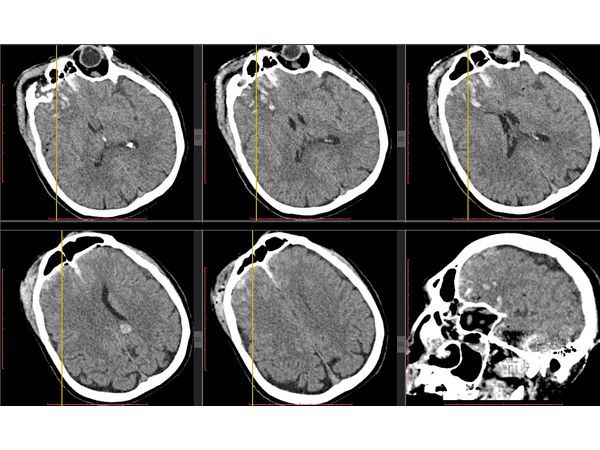

КТ головного мозга в первые сутки: выявлен линейный перелом лобной кости, переходящий на основание передней черепной ямки, и очаги ушиба полюсных отделов правой височной и лобной долей головного мозга (II вид по Корниенко), травматическое субарахноидальное кровоизлияние. Также выявлен двусторонний перелом нижней челюсти.

КТ головного мозга на вторые сутки: выявлена трансформация очага ушиба правой лобной доли во внутримозговую гематому (агрессивный очаг ушиба головного мозга).

После операции состояние пациента постепенного восстановилось до ясного. На третьи сутки после операции проведена контрольная КТ головного мозга.